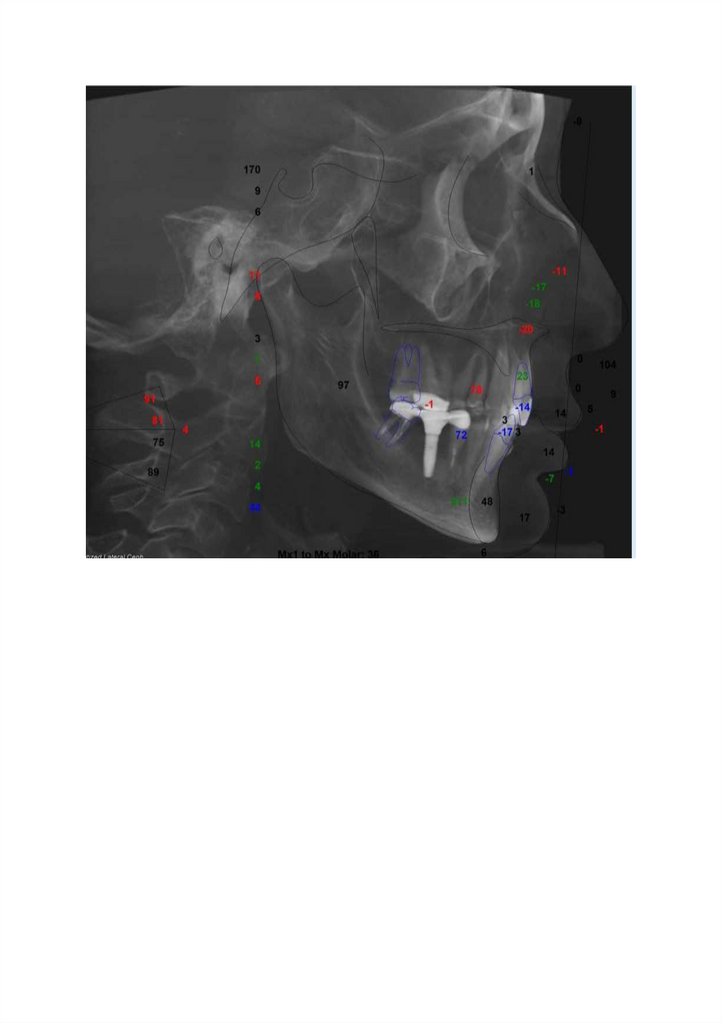

Соотношение че/иостей в сагиттальной плоскости.

Межапикальный угол (<ANB) - 5,1», что соответствует соотношению челюстей по II скелетному классу (N = 2» ± 2»).

Угол Бета (< Beta Angle) - 23,8». что соответствует соотношению челюстей по II скелетному классу (N = 31» t 4»)

Параметр Wits (Wits Appraisal.) - 4,8 мм, что указывает на наличие диспропорции в расположении апикальных базисов

верхней и нижней челюстей в сагиттальной плоскости и говорит за II скелетный класс (N * -0,4 мм * 2,5 мм). Соотношение

челюстей по методике Sassouni говорит за II скелетный класс — базальная дуга проходит на 3,6 мм кпереди от точки В (N =

0 мм ± 3 мм).

Параметр APDI, указывающий на дисплазию развития челюстей в сагиттальной плоскости, равен 77,2» и говорит за I

скелетный класс (N * 81,4* 1 5»).

Размер И положение верхней челюсти.

Длина основания верхней челюсти (PNS-A) - 47,9 мм, что соответствует норме (N я 48,9 мм ± 3,5 мм).

Ширина основания верхней (J-J) челюсти - 56,5 мм, что соответствует сужению (N = 60 мм t 3 мм): справа - 28,6 мм, слева 27,9 мм (N = 30 мм t 1,5 мм).

Положение верхней челюсти по сагиттали (<SNA) - 81,7», что соответствует норме (N = 82» ± 3«).

Положение верхней челюсти по вертикали (<SN-Palatal Plane) - 8,7», что соответствует нормоинклинации (N = 8® ± 3»), Roll

ротация влево (против часовой стрелки).

Yaw ротация отсутствует.

Размер и положение нижней челюсти.

Длина тела нижней челюсти (бо-Ме): справа - 81,3 мм, слева - 79,7 мм (N = 82 мм ± 5 мм). Длина тела нижней челюсти

справа на 1,6 мм больше, чем слева.

Длина ветви нижней челюсти (Co-Go): справа - 57,2 мм, слева - 47,7 мм (N = 56 мм ± 4 мм). Длина ветви нижнеи челюсти

справа на 9,5 мм больше, чем слева.

Гониальный угол (<Ar-Go-Me): справа - 128,8», слева - 134,2* (N = 130» ± 5«). Гениальный угол справа на 5,4» меньше, чем

слева.

Ширина базиса нижней челюсти (Md-Md) - 53,6 мм, что соответствует норме (N = 55 мм ± 3 мм).

Положение нижней челюсти по сагиттали (<SNB) - 76,6», что соответствует ретрогнатии (N = 80* ± 3*).

Положение нижней челюсти по вертикали (<MP-SN) - 34*, что соответствует нормоинклинации (N = 32* ± 4«). Смещение

подбородка влево на 7,9 мм.

Roll ротация отсутствует.

Yaw ротация вправо (по часовой стрелке).

Вертикальные параметры.

Вертикальное соотношение лица (N-ANS\ANS-Gn) гармоничное - 0,77 (N = 0,8 ± 0,09).

Отношение задней высоты лица к передней (S-Go/N-Gn) - 64,6% (N = 63% ± 2%).

Высота нижней трети лица по Ricketts (<ANS-Xi-Pm) - 43,4*, что соответствует норме (N = IVP 45.9* ± 5.5*).

Параметр ODI - 78,3», что соответствует норме (N = 74,5* ± 5*).

Положение резцов. ___

Межрезцовый угол: справа -165,8*, слева - 165,1* (N = 130 ±6 ).

Ретрузия 1.1 на 17,2*, ретрузия 2.1 на 15,2* (N = 110* ± 5*). Ретрузия

3.1 на 10,2*, ретрузия 4.1 на 8,9* (N = 95* ± 5*).

- 53,6 мм. Фактическая ширина базиса верхней челюсти - 56,5 мм. Требуемая ширина

Penn анализ.

Ширина базиса нижней челюсти

базиса верхней челюсти - 58,6 мм. ___, .

Дефицит ширины скелетного базиса верхней челюсти составляет 2,1 мм

Воздухоносные пути.

Уменьшения объема воздухоносных путей не выявлено.